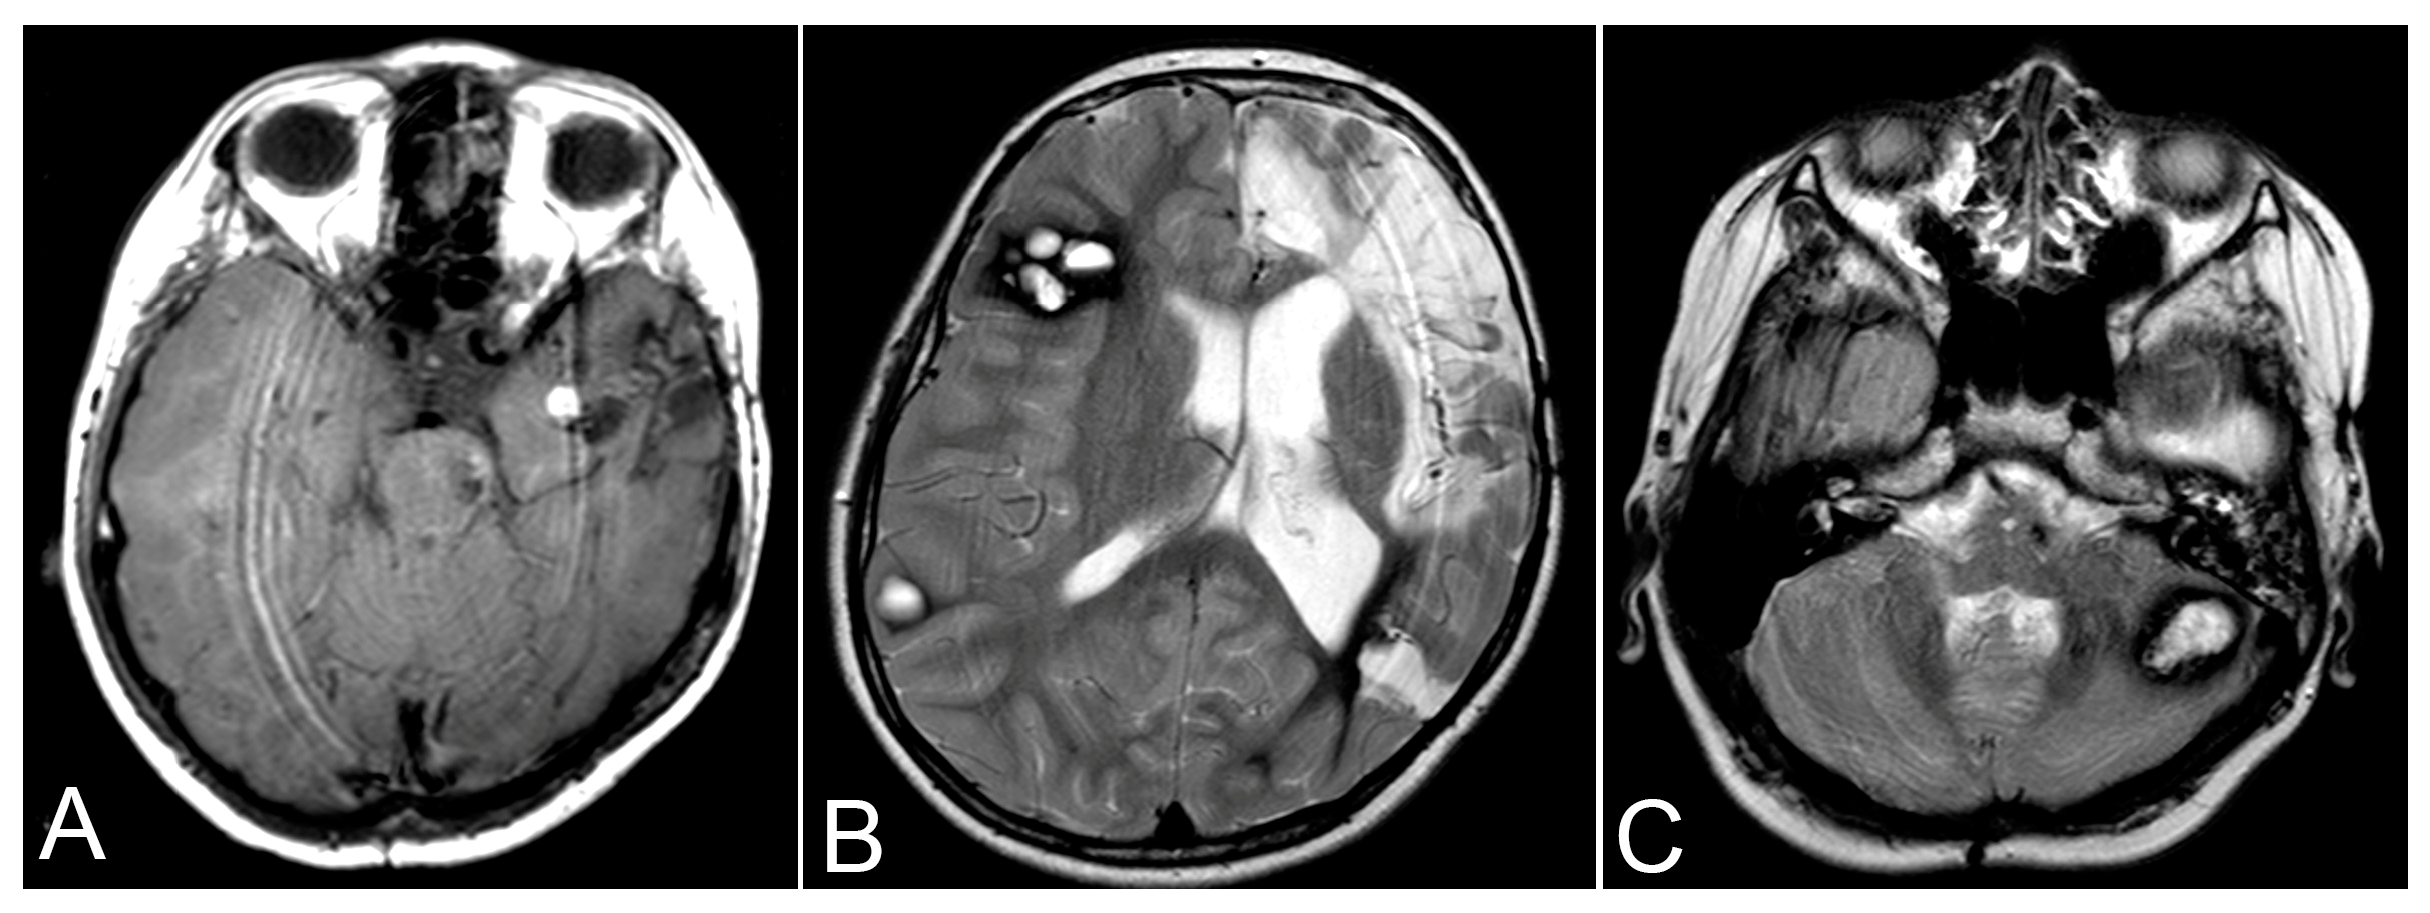

| 3rd admission | 1 August 2017 | MRI (Axial T2) | Hemorrhage from CCM in the left posterior temporal lobe, enlargement of the left anterior temporal CCM |

| 3rd admission | 24 August 2017 | CT Scan | Post-surgical removal of temporal CCM and hematoma |

| 4th admission | 30 April 2019 | MRI | New pontine hematoma, enlargement of the left anterior temporal CCM |